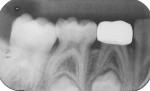

A pink ceramic "try-in" crown from the manufacturer was placed over the prepared tooth for trial sizing and to assess the need for refinement of the preparation. In this case, the buccal surface required slightly more reduction for the crown to be fully seated (Figure 7). Following the additional preparation, luting cement (BioCem Universal BioActive Cement®, NuSmile) was blended and placed within the selected tooth-colored crown form, and it was then pressed into place with finger pressure. A curing light was applied to the occlusal aspect for 10 seconds and then to the buccal and lingual aspects for 10 seconds each (Figure 8). This cement undergoes chemical polymerization in addition to light polymerization; therefore, complete hardening is assured. After light curing, the excess marginal cement was removed with a Hollenback carver (Figure 9). In addition, careful explorer probing and knotted dental tape are useful to remove interproximal increments of cement. At 46 months after placement, the zirconia crown demonstrated excellent occlusion and esthetics (Figure 10 and Figure 11). The 46-month postoperative radiograph revealed a distal margin that was slightly overhanging, but it proved to be of no consequence to the patient (Figure 12).